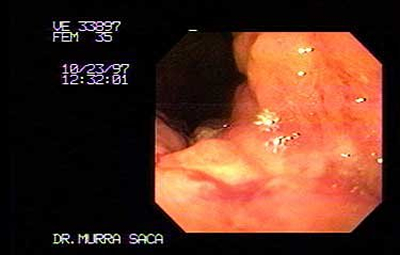

Paciente femenina de 35 años:

Consulta por dolor abdominal de dos meses de evolución, pérdida de peso e ictericia, vómitos de contenido alimenticio con fetidez. Dicha paciente había emigrado hacia los Estados Unidos de Norte América, en sus principios fue diagnosticada como Hepatitis viral A, manejada ambulatoriamente. Pero su cuadro empeoraba por lo que decidió regresar a su país de origen El Salvador.

Fotografía del caso anterior:

Carcinoma Gástrico que ha infiltrado toda la cámara gástrica, se observa el cardias por retroflexión el cual es infiltrado por dicho carcinoma parte negra es el Endoscopio.